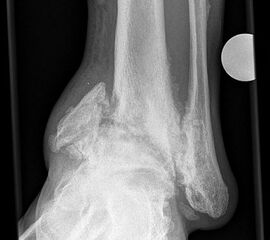

Abbildung 5

DNOAP Typ IV (Abb. 5)

Dieser Typ ist charakterisiert durch eine Nekrotisierung des oberen Sprunggelenkes (Talus, distale Tibia und Fibula).

DNOAP Typ V (Abb. 6)

Die DNOAP Typ V betrifft das talokalkaneare Gelenk. Es ist vor allem der dorsale Anteil des unteren Sprunggelenkes betroffen. Es kommt zu einer Kippung des Rückfusses. Bei intakter Fibula findet diese in eine Varusstellung mit Luxation nach medial statt, teilweise entwickeln sich aber auch Frakturen in der distalen Fibula mit Abkippung in eine Valgusstellung. Um den Fuß ins Lot zurückzubringen, sind Resektionsarthroplastiken oder Arthrodesen erforderlich. Eine operative Behandlung ist allerdings mit einigen potentiellen Problemen behaftet. Arthrodesen und Osteosynthesen am neuropathischen Fuß bauen meist nicht oder erst nach Monaten der Ruhigstellung und Entlastung durch (siehe auch Kapitel „Operative Therapie der Diabetischen Neuroarthropathie). Auf der anderen Seite besitzt die oft extreme Fehlstellung ein hohes Risiko für die Entwicklung eines Malum perforans mit dem Risiko der Osteomyelitis und dem Verlust des gesamten Fußes. Gelingt konservativ keine entsprechende Stabilisierung des Rückfusses, so kann unter Abwägung der Risiken durchaus eine operative Intervention indiziert sein 20.